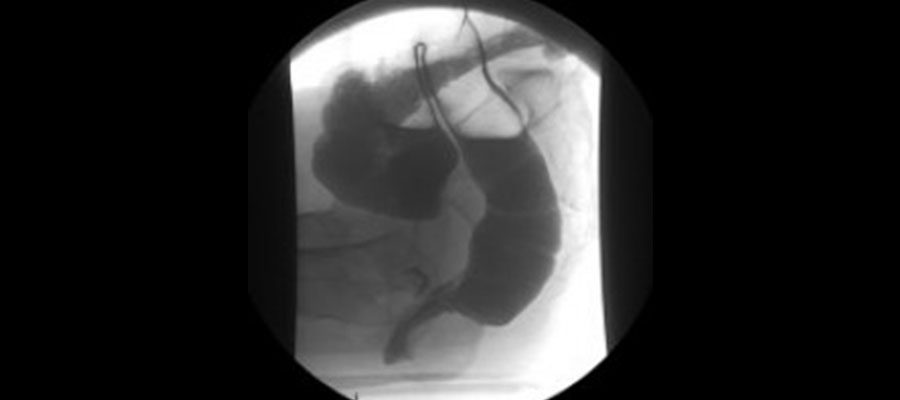

Defekografi

Defekografi Nedir?

Defekografi boşaltım yollarında meydana gelen problemleri anlamak ve doğru tedaviyi bulmak için yapılan bir görüntüleme türüdür. Kabızlık, idrar kaçırma gibi problemler pek çok insanın hayatını olumsuz yönde etkiler. Günlük hayatını bu sebepler yüzünden devam ettiremez hale gelen çok sayıda kişi öncelikle bir doktora başvurur.

Defekografi çekimi yapılmadan önce doktor hastayı detaylı bir şekilde muayene eder. Daha sonra eğer gerekli görülürse çekim yapılması talep edilir. Defekografi çekimi esnasında manyetik rezonans cihazlarından yararlanılır. Manyetik rezonans cihazları radyasyonsuz bir görüntüleme tekniğidir ve vücudun tüm  bölgelerindeki sorunları detaylı şekilde gösterir